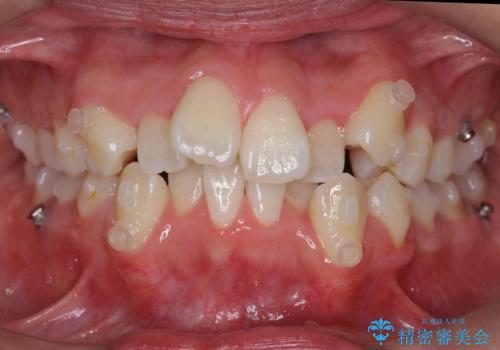

八重歯 抜かずにマウスピース矯正治療

- 八重歯を主訴に来院。

(1)口元を下げるなら、上下左右抜歯でワイヤー矯正

(2)奥歯を後ろに下げ、歯並びを拡大し、歯を少し削って抜かずにインビザライン矯正 矯正用ミニスクリュー併用 口元は下がらない

の選択肢から選んでもらいました。

目立たない装置希望とのことで、(2)を選択されました。

抜歯をしていないので口元は変わっていません。

八重歯も重症でなければインビザラインでも並びを歯を抜かずに整えることができます。